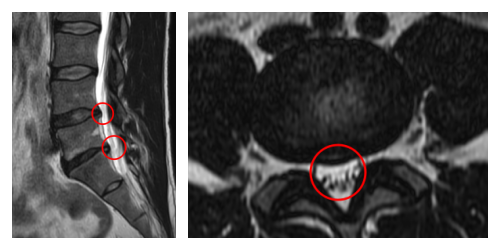

┃検査・診断

赤い枠で示されている部分(L4/5, L5/S)にヘルニアが認められました。